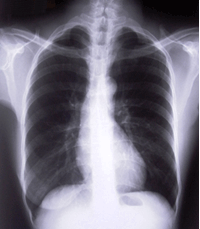

(一)X线检查 慢支早期可无异常,随病情发展引起支气管壁增厚或肺间质炎症与纤维化,可出现两肺纹理增多、增粗、紊乱,呈网状或条索状阴影,以下肺野较明显。合并感染时肺纹理周围可有斑点状模糊阴影。肺气肿时可显示胸廓扩张,肋间隙增宽,膈降低且变平,两肺野透亮度增加。